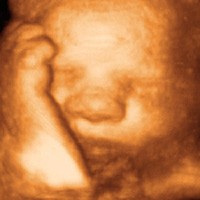

Sneak Peek Ultrasound is just one of many businesses across the country opening to meet the demand for “fetal keepsake videos” from expectant couples. Typically, parents-to-be receive a flat, grainy black-and-white image of their growing baby from their doctor after a standard diagnostic ultrasound at 18 weeks. But parents are increasingly shelling out $100-$300 for live-3D images of their babies later in their pregnancies in order to obtain golden-hued videos and photographs that can capture a yawn or a smile and reveal distinctive features such as the baby’s eyes, nose, and chin.

“It is clear that women want this service, they want that connection,” said Kelli Twiss, who runs Sneak Peek’s Salem branch. Twiss, a mother of four, wished she had had the chance to bond more closely with her babies when she was pregnant. “For some people I don’t think the reality hits until they see a little baby’s face.” She and her husband Dan, a carpenter, decided to open their branch of Sneak Peek Ultrasound a year ago after buying a used General Electric ultrasound machine and hiring a certified ultrasound technician to run it.